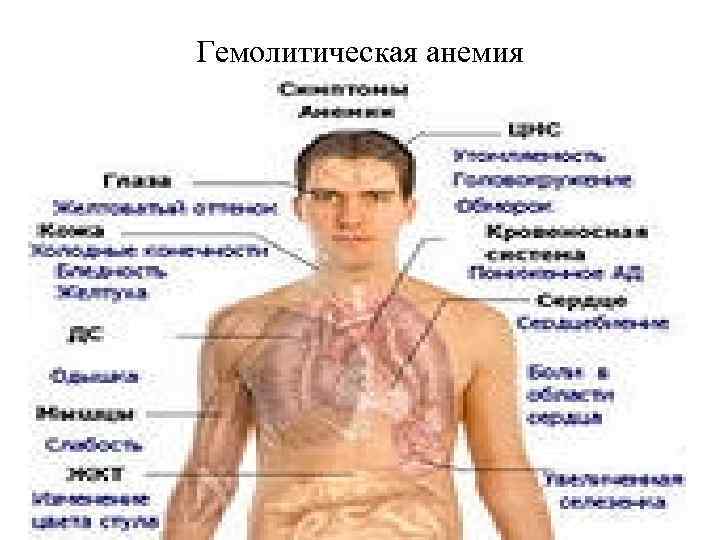

Гемолитическая анемия

Гемолитические анемии Гемолитические анемии - это группа заболеваний, при которых уменьшается средняя продолжительность жизни эритроцитов. В большинстве случаев костный мозг функционирует нормально; возможно образование адекватного числа новых эритроцитов, с повышением числа ретикулоцитов. Гемолитические анемии - группа наследственных и приобретенных заболеваний, характеризующихся повышенным внутриклеточным (гемолиз в клетках фагоцитарной системы) или внутрисосудистым (гемолиз в сосудистом русле при участии комплемента) разрушением эритроцитов. Диагностические признаки заболевания обусловлены: - ускоренным распадом эритроцитов (уменьшение времени жизни эритроцитов, повышение содержания сывороточного ЛДГ, восстановленного гаптоглобина), - увеличением активности костного мозга (эритроидная гиперплазия, ретикулоцитоз)

Гемолитические анемии Анемии вследствие усиленного кроверазрушения (гемолитические): - наследственные: 1) связанные с нарушением структуры мембраны эритроцитов (микросфероцитоарная анемия Миньковского – Шаффара, овалоцитоз, акантоцитоз), 2) связанные с дефицитом ферментов в эритроцитах, 3) связанные с нарушением синтеза гемоглобина (серповидноклеточная анемия, гемоглобинозы, талассемия) - приобретенные: 1) аутоиммунные, 2) пароксизмальная ночная гемоглобинурия, 3) лекарственные, 4) травматические и микроангиоспастические, 5) вследствие отравления гемолитическими ядами и бактериальными токсинами. - анемии смешанные